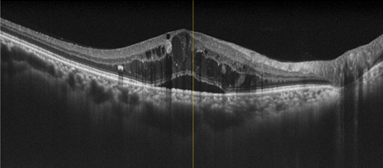

網膜の層構造を断面的に観察できます。

黄斑浮腫(網膜のむくみ)の状態がわかります。